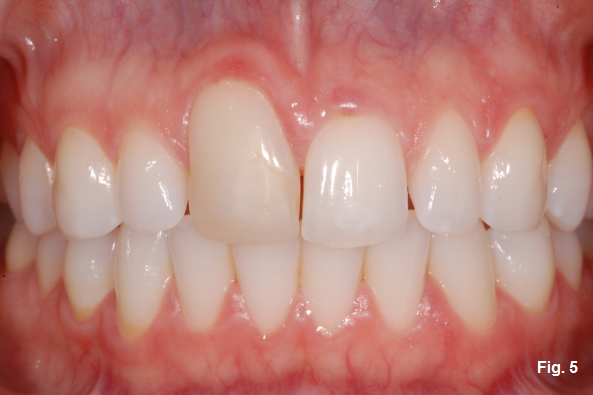

Although the tooth could be extracted now in preparation for a single-tooth implant, the decision was made to leave the tooth and restore the incisal edge length with composite (Fig. 4).

The patient and her family knew that the composite was an interim restoration and that the tooth would require extraction and implant placement in the future. The question of when depends on the rate at which the resorption progresses. The tooth lasted another 10 years in this patient before it required extraction (Fig. 5).